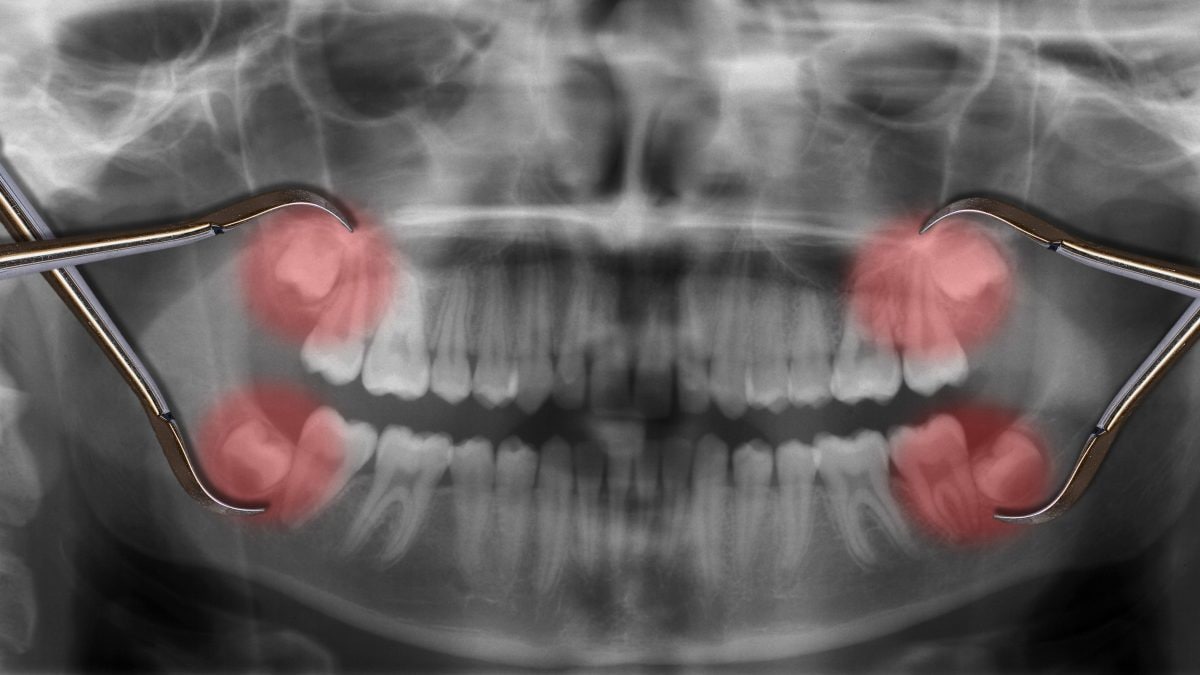

Una persona su quattro, oggi, manca completamente di almeno uno dei denti del giudizio. Secondo alcuni scienziati, questo potrebbe avere a che fare con i geni ereditati dai genitori. Altri, invece, sostengono che la mancanza dei denti del giudizio sia un vantaggio evolutivo per gli esseri umani moderni. Avendo le ossa craniche più strette ed esili delle altre specie di Ominini, infatti, abbiamo anche meno spazio per la crescita dei denti. È proprio a causa della mancanza di spazio, che talvolta i denti del giudizio possono rimanere bloccati all'interno della mascella e spuntare parzialmente o non spuntare affatto, andando a spingere sugli altri denti dell’arcata.

Nei casi in cui i denti del giudizio non crescano verticalmente ma spingano in senso orizzontale, dentro l’osso mascellare, proviamo dolore e siamo più facilmente soggetti a carie o infiammazioni gengivali, motivo per cui vengono estratti da un dentista. E ciò si verifica più spesso nella mascella inferiore che in quella superiore.